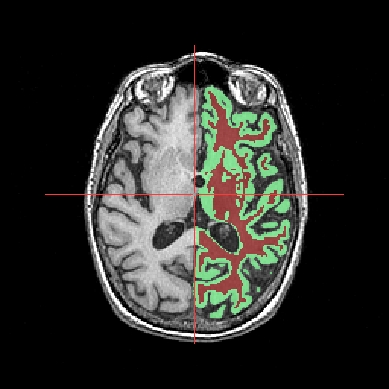

In the following example, 3 objects are loaded in Anatomist:

Object1 (O1): anatomy

Object2 (O2): regions of interest graph drawn from the anatomy. So these 2 objects are in the same referential.

Object3 (O3): nomenclature to associate colors to regions of interest according to their name. This object does not have to be put in a window. Link between names in the nomenclature and in regions of interest is done automatically by Anatomist.

These 2 objects are in the same coordinates system, so they will be placed in the same referential, that is to say they will have the same color circle (red by default).

Superimposing an anatomy and regions of interest¶